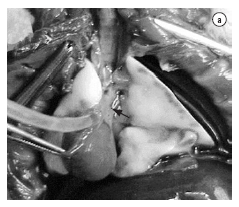

O animal receptor era sedado, anestesiado e intubado via orotraqueal. Posteriormente, eram selecionados os parâmetros ventilatórios previamente descritos para o doador e canulada a artéria carótida direita ou esquerda, com um Abocath® #24 para monitorização hemodinâmica. O animal, em decúbito lateral direito, era submetido a uma toracotomia póstero-lateral esquerda no 5º espaço intercostal. Após liberado o ligamento pulmonar, o pulmão esquerdo era exteriorizado e mantido fora da cavidade torácica por um clipe metálico (Figura 2a). Depois de isoladas as estruturas hilares (artéria, brônquio e veia), estas eram clampeadas com um clampe hemostático. Estas estruturas eram envolvidas com um fio de sutura de 7-0 ou 8-0 pronto para ser amarrado assim que cada estrutura fosse canulada. O implante iniciava-se através da secção da parede lateral da artéria na sua porção ventral, progredindo-se cuidadosa e lentamente o cuff da artéria do doador para dentro da artéria receptora e a fixação desta com aquele fio de sutura colocado previamente ao redor da artéria (Figura 2b). Este mesmo procedimento era realizado para o brônquio e a veia, respectivamente e nesta ordem. Uma vez implantado o pulmão, procedia-se com a abertura do clampe brônquico, seguido da veia e artéria respectivamente (Figura 2c), com posterior retirada do pulmão esquerdo do receptor. Após o término do transplante, era realizado o clampeamento do pulmão contralateral. Esta variante do modelo original permite a avaliação exclusiva do pulmão transplantado (Figura 2d). Este procedimento é realizado pela mesma incisão da toracotomia, retraindo-se o pulmão transplantado em projeção anterior com o auxílio de um cotonete, disseca-se a face mediastinal posterior, permitindo a identificação do hilo pulmonar direito e facilitando o seu clampeamento. A oclusão do hilo pulmonar direito pode ser realizada em bloco ou efetuada apenas a ligadura da artéria pulmonar direita. Esta variação depende exclusivamente do objetivo do estudo a ser realizado. Quando realizada a oclusão total do hilo pulmonar, deve-se reduzir o volume de ar corrente para 5 mL/kg, para evitar a hiperinsuflação do pulmão transplantado e conseqüente lesão induzida pelo ventilador. Na eventualidade de ligadura da artéria pulmonar contralateral apenas, o volume corrente permanece o mesmo. Também podem ser realizados clampeamentos temporários da artéria pulmonar direita com o objetivo de coletar gasometrias arteriais que representem apenas a troca gasosa do pulmão transplantado. Após realizado o transplante e o clampeamento hilar contralateral, o pulmão é insuflado e a parede torácica fechada por planos. Terminado o período de observação, é realizada a extração do bloco cardiopulmonar sendo este fixado em paraformaldeído a 4% ou armazenado a -70 °C.